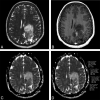

Background and purpose: Oligodendrogliomas are tumors that have variable WHO grades depending on anaplasia and astrocytic components and their treatment may differ accordingly. Our aim was to retrospectively evaluate imaging features of oligodendrogliomas that predict tumor grade.

Materials and methods: The imaging studies of 75 patients with oligodendrogliomas were retrospectively reviewed and compared with the histologic grade. The presence and degree of enhancement and calcification were evaluated subjectively. rCBV and ADC maps were measured. Logistic linear regression models were used to determine the relationship between imaging factors and tumor grade.

Results: Thirty of 75 (40%) tumors enhanced, including 9 of 46 (19.6%) grade II and 21 of 29 (72.4%) grade III tumors (P < .001). Grade III tumors showed lower ADC values compared with grade II tumors (odds ratio of a tumor being grade III rather than grade II = 0.07; 95% CI, 0.02-0.25; P = .001). An optimal ADC cutoff of 925 10(-6) mm(2)/s was established, which yielded a specificity of 89.1%, sensitivity of 62.1%, and accuracy of 78.7%. There was no statistically significant association between tumor grade and the presence of calcification and perfusion values. Multivariable prediction rules were applied for ADC < 925 10(-6) mm(2)/s, the presence of enhancement, and the presence of calcification. If either ADC < 925 10(-6) mm(2)/s or enhancement was present, it yielded 93.1% sensitivity, 73.9% specificity, and 81.3% accuracy. The most accurate (82.2%) predictive rule was seen when either ADC < 925 10(-6) mm(2)/s or enhancement and calcification were present.

Conclusions: Models based on contrast enhancement, calcification, and ADC values can assist in predicting the grade of oligodendrogliomas and help direct biopsy sites, raise suspicion of sampling error, and predict prognosis.